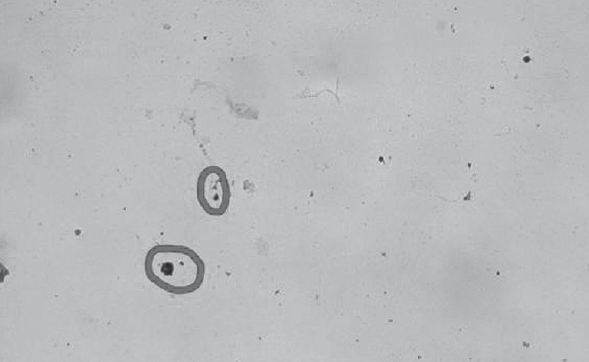

С целью совершенствования методов лабораторной диагностики в Центре было обследовано 10 ВИЧ-инфицированных детей с использованием ИГЦХ. В результате у половины диагноз был подтвержден (см. таблицу, рис. 1, 2), что совпадает с данными литературы, которые утверждают, что чувствительность ИГЦХ у больных может быть ниже при применении АРВТ [29]. Обращает внимание, что почти у всех больных вирусная нагрузка была ниже порога детекции, кроме одного.

Рис. 1. Экспрессия антигена ВИЧ-1 (р24) в клетках эпителия у больного 10/163, 14 лет. Мазок со слизистой оболочки небных миндалин. Иммуногистоцитохимическая окраска, слабая докраска метиленовым синим. Об. ×20

Fig. 1. Expression of HIV-1 antigen (P24) in epithelial cells in a 10/163, 14-year-old patient. Smear from the mucous membrane of the Palatine tonsils. Immunohistocytochemical coloration, weak pre-paint with methylene blue

Рис. 2. Экспрессия антигена ВИЧ-1 (р24) в клетках эпителия у пациента 16/29, 7 лет. Мазок со слизистой оболочки задней стенки ротоглотки. Иммуногистоцитохимическая окраска, слабая докраска метиленовым синим. Об. ×20

Fig. 2. Expression of HIV-1 antigen (P24) in epithelial cells in a 16/29, 7-year-old patient. Smear from the mucous membrane of the posterior wall of the oropharynx. Immunohistocytochemical coloration, weak pre-paint with methylene blue